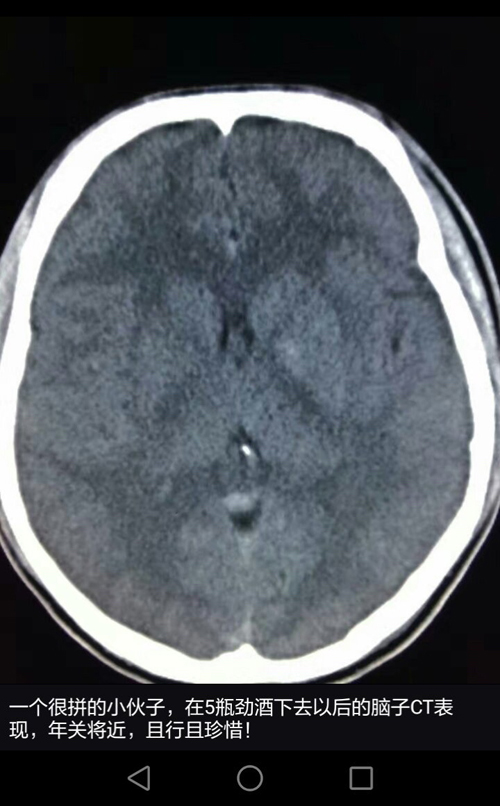

正常的脑部CT,可见清晰的脑沟。

在医院ICU(重症监护室)的办公室,记者见到了当时的接诊医生县第一医院重症监护室主治医生王平。他告诉记者,病人是在1月4日晚10点左右醉酒回家,次日早上7点多被家人送进急诊。这位小伙子被送进医院时已经深度昏迷,双侧瞳孔出现不等大情况,舌根后坠,肺内有渗出性病变,考虑出现了误吸,同时脑CT显示他的脑沟消失,提示酒精中毒的急性作用,伴脑实质缺氧。王平介绍说,酒精中毒,也就是我们常说的醉酒,不少人会出现气道保护能力下降的情况,因此在呕吐的时候,容易导致胃内容物逆流进入咽喉腔及气管内,造成这种误吸情况。